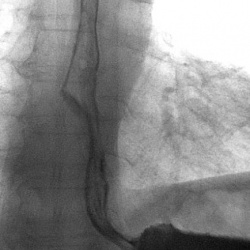

Мужчина 60 лет. Дисфагия. Боль при глотании. Эндоскопически - резкое сужение входа в пищевод, пройти не удалось.

Пациент за 70, жалобы на затруднение прохождения пищи по пищеводу, рвота. Похудел на 30 кг из-за проблем с питанием. Обследывался и в онкодиспансере...Короче, никто не предлагает никаких решений....